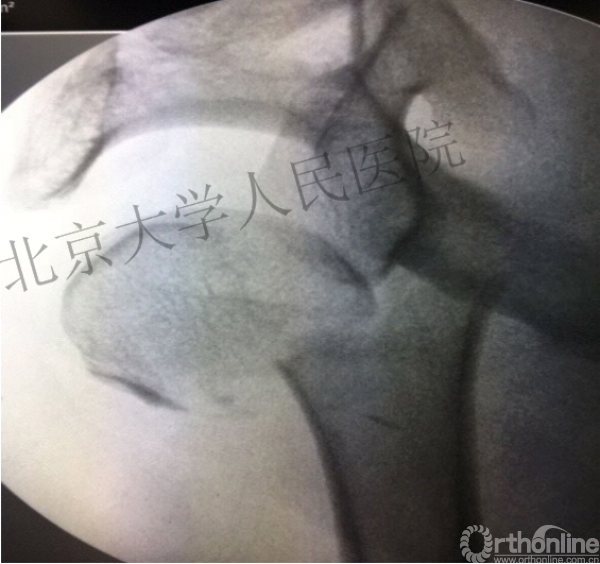

内侧皮质粉碎,低位外科颈骨折,肱骨头-干角维持困难。

术后复位丢失,肱骨头内翻畸形。

能否该偏心固定(钢板)为髓内固定,增加力臂?

此时对比髓内钉是不是有很大优势?